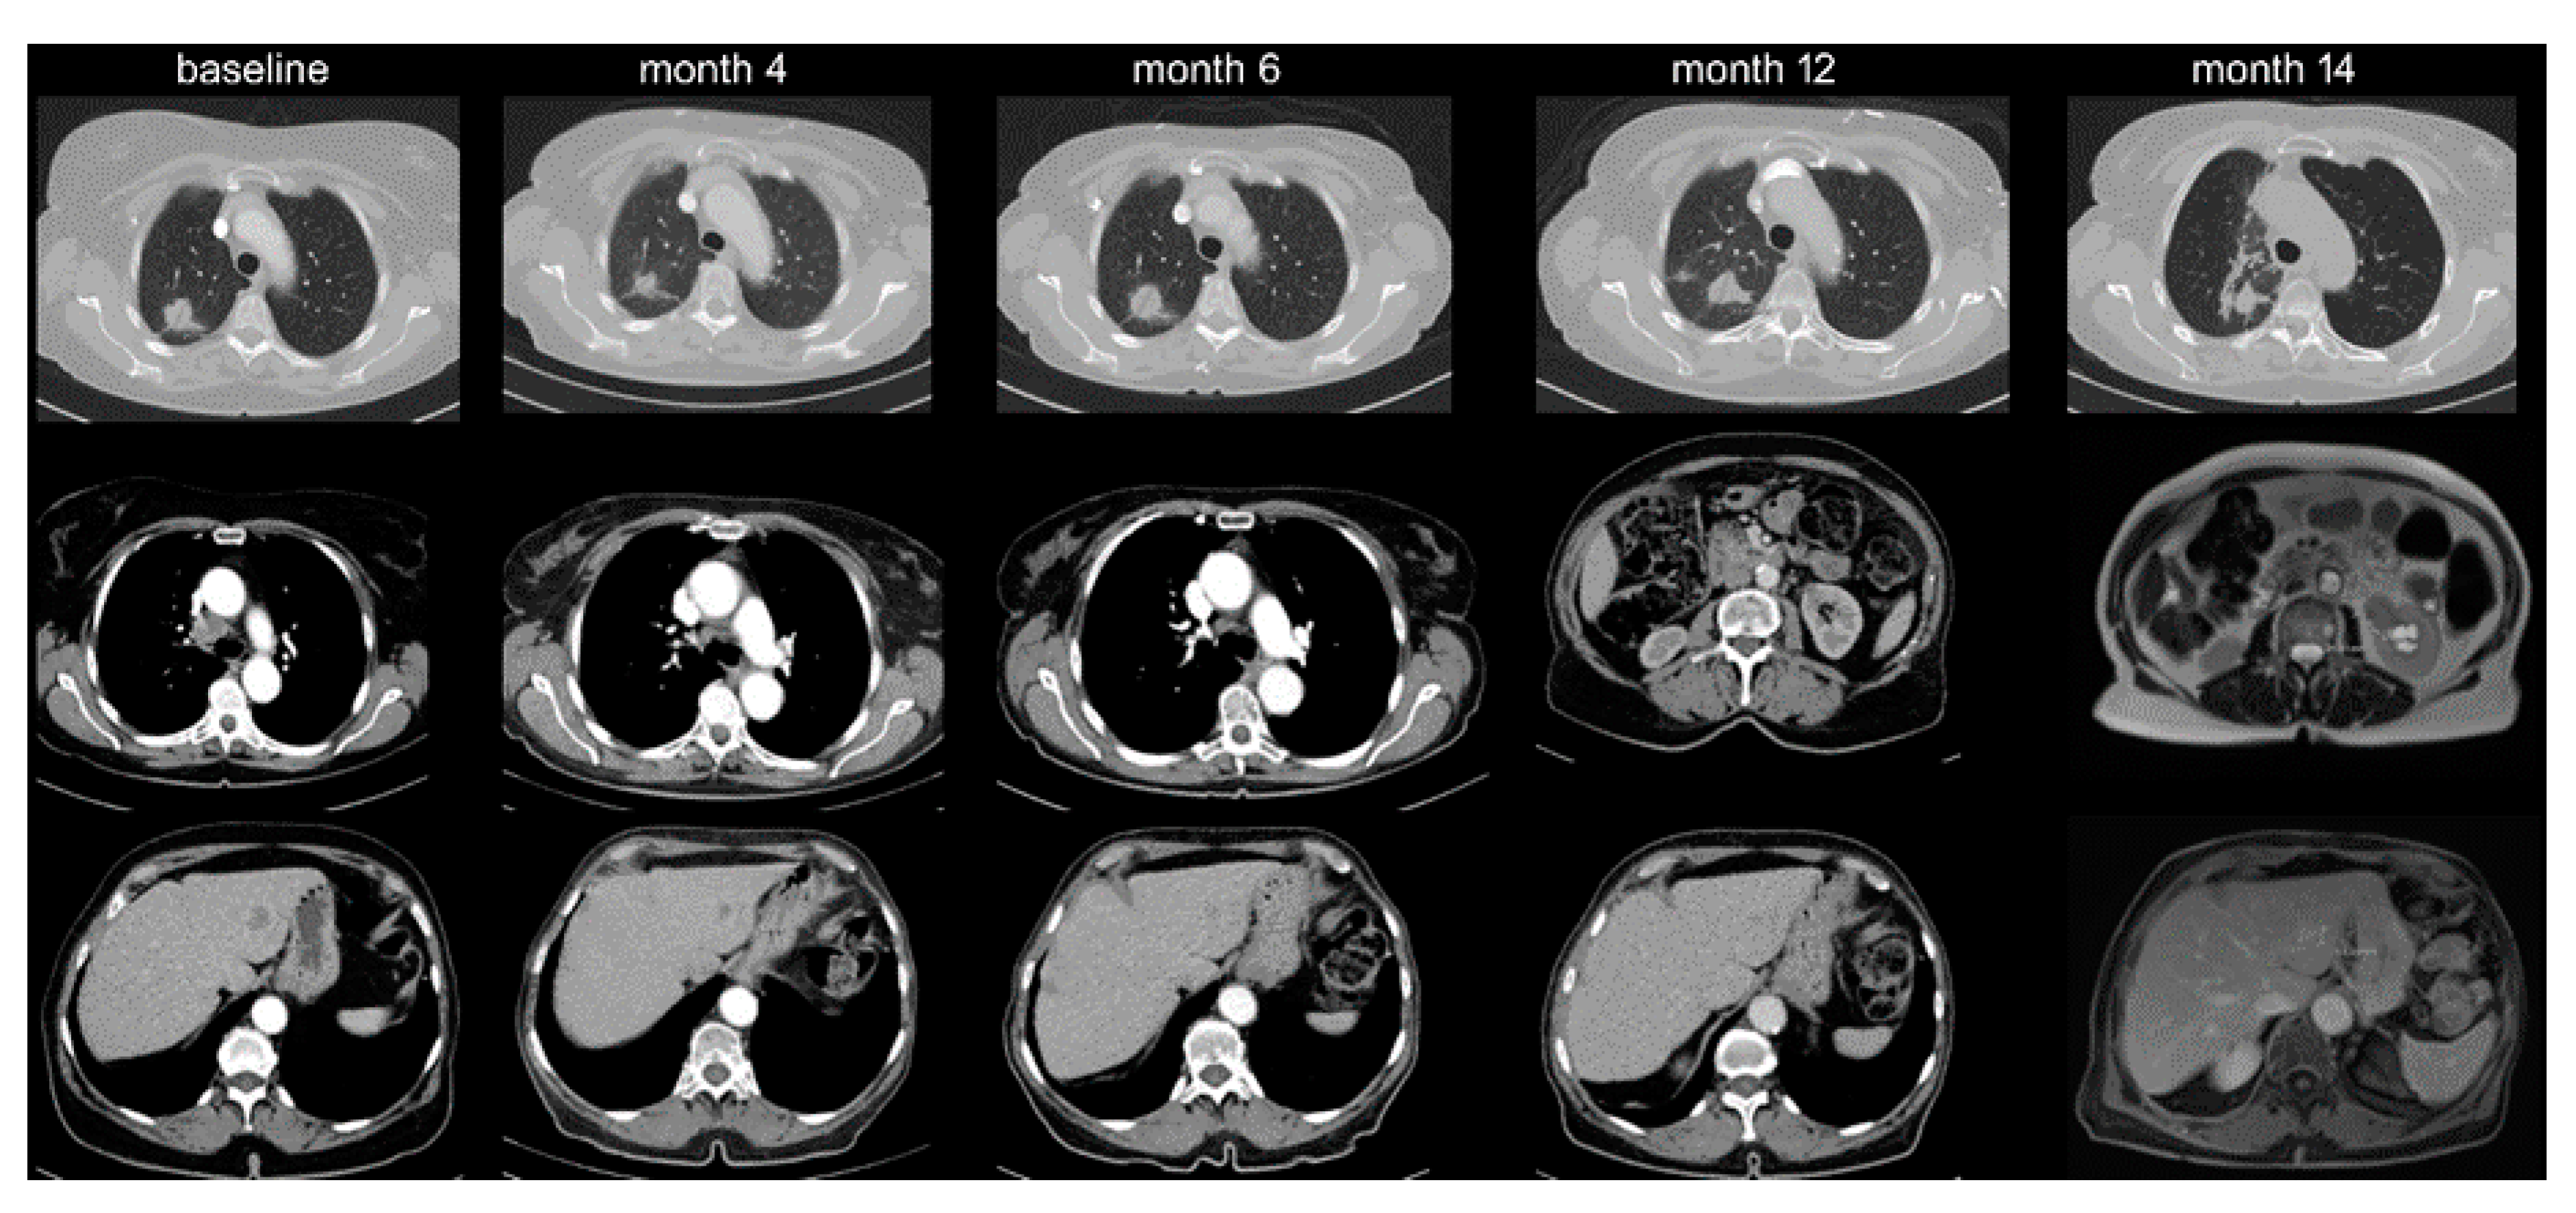

- Schmid, S.; Diem, S.; Li, Q.; Krapf, M.; Flatz, L.; Leschka, S.; Desbiolles, L.; Klingbiel, D.; Jochum, W.; Früh, M. Organ-specific response to nivolumab in patients with non-small cell lung cancer (NSCLC). Cancer Immunol. Immunother. 2018, 67, 1825–1832. [Google Scholar] [CrossRef] [PubMed]

- Ren, Y.; Dai, C.; Zheng, H.; Zhou, F.; She, Y.; Jiang, G.; Fei, K.; Yang, P.; Xie, N.; Chen, C. Prognostic effect of liver metastasis in lung cancer patients with distant metastasis. Oncotarget 2016, 7, 53245–53253. [Google Scholar] [CrossRef]

- Tumeh, P.C.; Hellmann, M.D.; Hamid, O.; Tsai, K.K.; Loo, K.L.; Gubens, M.A.; Rosenblum, M.; Harview, C.; Taube, J.M.; Handley, N.; et al. Liver Metastasis and Treatment Outcome with Anti-PD-1 Monoclonal Antibody in Patients with Melanoma and NSCLC. Cancer Immunol. Res. 2017, 5, 417–424. [Google Scholar] [CrossRef] [Green Version]